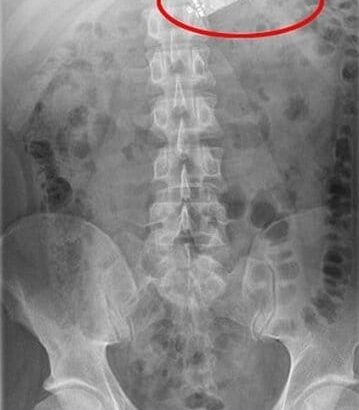

Các bác sĩ sau khi chụp X-quang quyết định phải phẫu thuật để lấy dị vật khỏi bụng bệnh nhân. Trước đó, người này có biểu hiện nôn trong 4 tiếng liên tục. Bệnh nhân kể lại với bác sĩ rằng vì cảm thấy quá buồn chán và căng thẳng, anh đã nuốt chiếc điện thoại di động của mình 6 tiếng trước đó.

Trước tình huống điện thoại có thể chui vào ruột bệnh nhân bất kì lúc nào, các bác sĩ ở bệnh viên Adelaide quyết định mổ khẩn cấp.

Ban đầu các bác sĩ dùng đèn soi để xác định vị trí và định gắp điện thoại qua đường thực quản. Tuy nhiên, ý định này không thành nên buộc phải phẫu thuật lấy điện thoại ra khỏi người bệnh nhân. Sau khi rạch một đường lớn trên bụng, dị vật đã được gắp thành công.